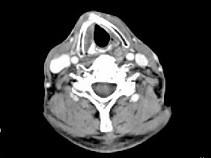

问题 男,63岁,咽喉部不适约一年,近2个月经常咳嗽,痰中带有血丝,CT如图所示,应诊断为 ( )

选项 A、声门上型喉癌 B、混合型喉癌 C、声门型喉癌 D、声门下型喉癌 E、梨状窝癌

答案 A